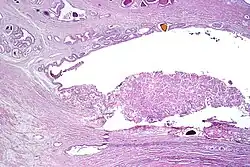

Example histopathologic preparation after prostatectomy.